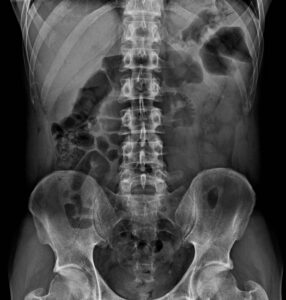

A myelogram is a specialized diagnostic imaging procedure that uses contrast dye injected into the spinal fluid, followed by CT imaging, to evaluate the spinal cord, nerve roots, and spinal canal. This advanced imaging technique provides detailed information that helps diagnose the cause of back pain, neck pain, and neurologic symptoms.

Myelograms diagnose spinal conditions by revealing abnormalities in the spinal canal, spinal cord, and nerve roots that may not be fully visible on standard imaging.

Myelograms are highly accurate for visualizing the spinal canal, nerve roots, and areas of compression.